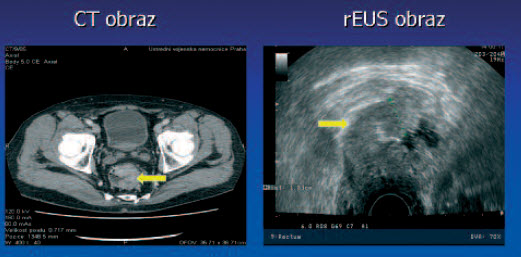

Tumor T2 N0

Tumor T2 N1